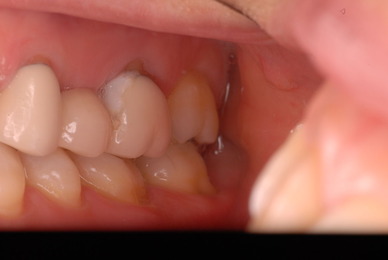

神経が死んでしまった歯は脆いのです。

重症の歯周病で削って上の歯とぶつからないようにしていた歯ですが

いつの間にか神経が死に歯の中が腐っていたようです。

それでヒビが入り割れてしまいました。